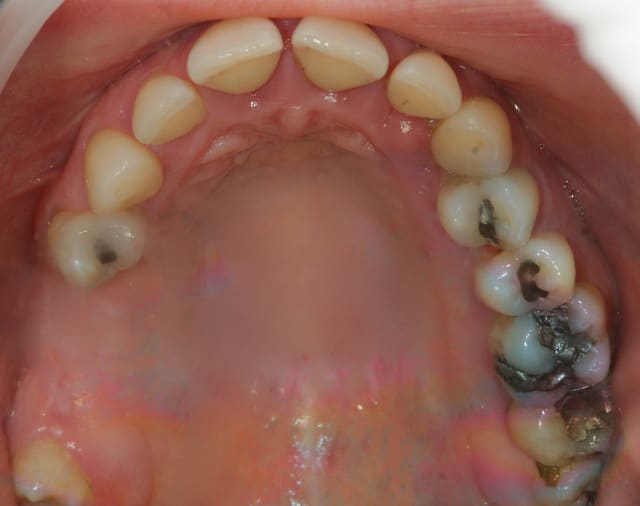

Principalement les lésions en forme de cuvettes que l'on retrouve en secteur 2 et 4. Cette forme de lésions permet une meilleure tenue du biomatériau et permet un afflux sanguin perpendiculairement à la paroi. C'est le même principe que la cicatrisation d'une alvéole intacte sans paroi manquante.

Théoriquement après cica, on peux esperer une réossification au mieux jusqu'à la limite haute de la cuvette.

Est ce une régénération parodontale que tu recherches ou un comblement d'un défaut osseux ?